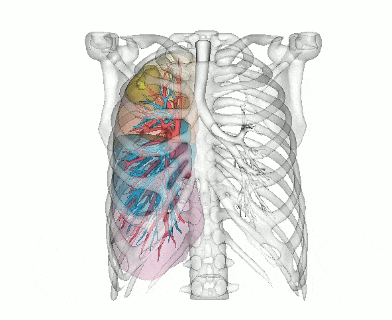

阿梵D——胸外CT三维重建结果

↑三维重建中肺结节位置信息

↑三维重建肺动静脉预览

↑三维重建肺动静脉及肺段整体预览